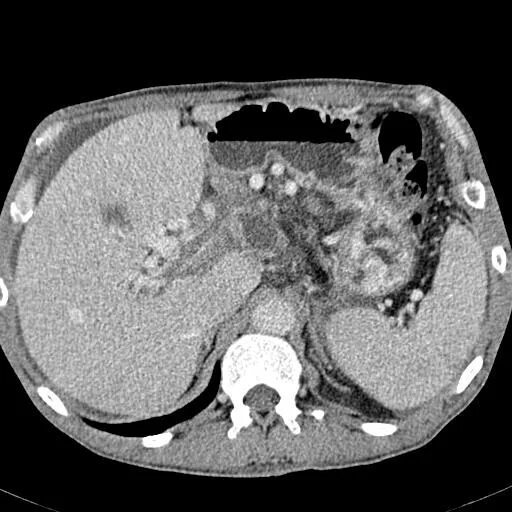

Подготовка к мрт печени